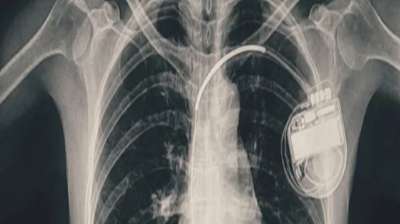

भोपाल में बच्ची के दिल की धड़कन धीमी पड़ी, डॉक्टरों ने पेसमेकर लगाकर बचाई जान

भोपाल। भोपाल मेमोरियल अस्पताल एवं अनुसंधान केंद्र (बीएमएचआरसी) के कार्डियोलॉजी विभाग ने एक दुर्लभ और चुनौतीपूर्ण चिकित्सा उपलब्धि हासिल की है। यहां 13 वर्ष की गैस पीड़ित आश्रित बालिका को...